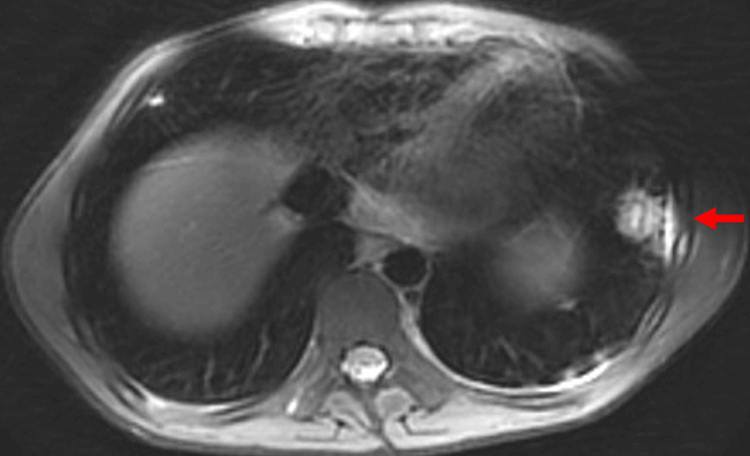

Subsequently, the patient developed bilateral foot edema, which progressed to the entire left lower extremity, associated with weight-bearing pain and tenderness over the medial posterior left knee. Doppler ultrasound ruled out deep vein thrombosis. MRI revealed distal left femoral osteomyelitis with a subperiosteal abscess (Figure 2). He underwent surgical joint washout and drainage.

Figure 2: Magnetic resonance showing distal left femoral osteomyelitis with subperiosteal abscess (red arrow).